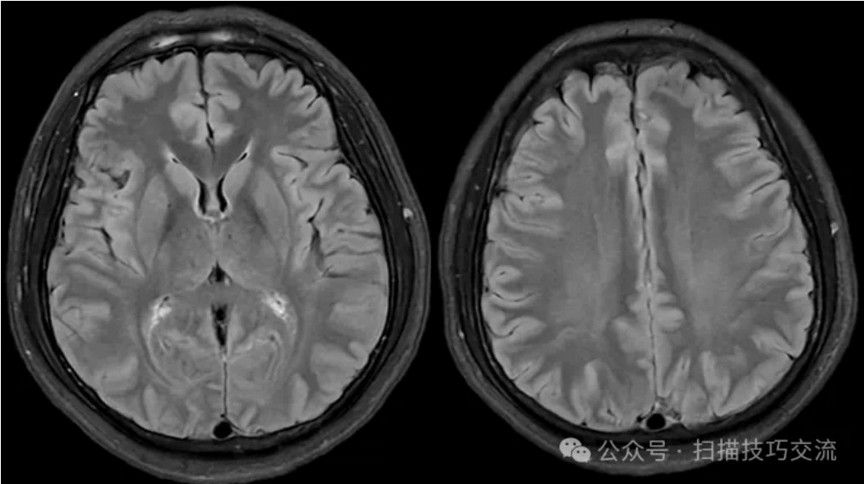

PC-MRV未见异常。